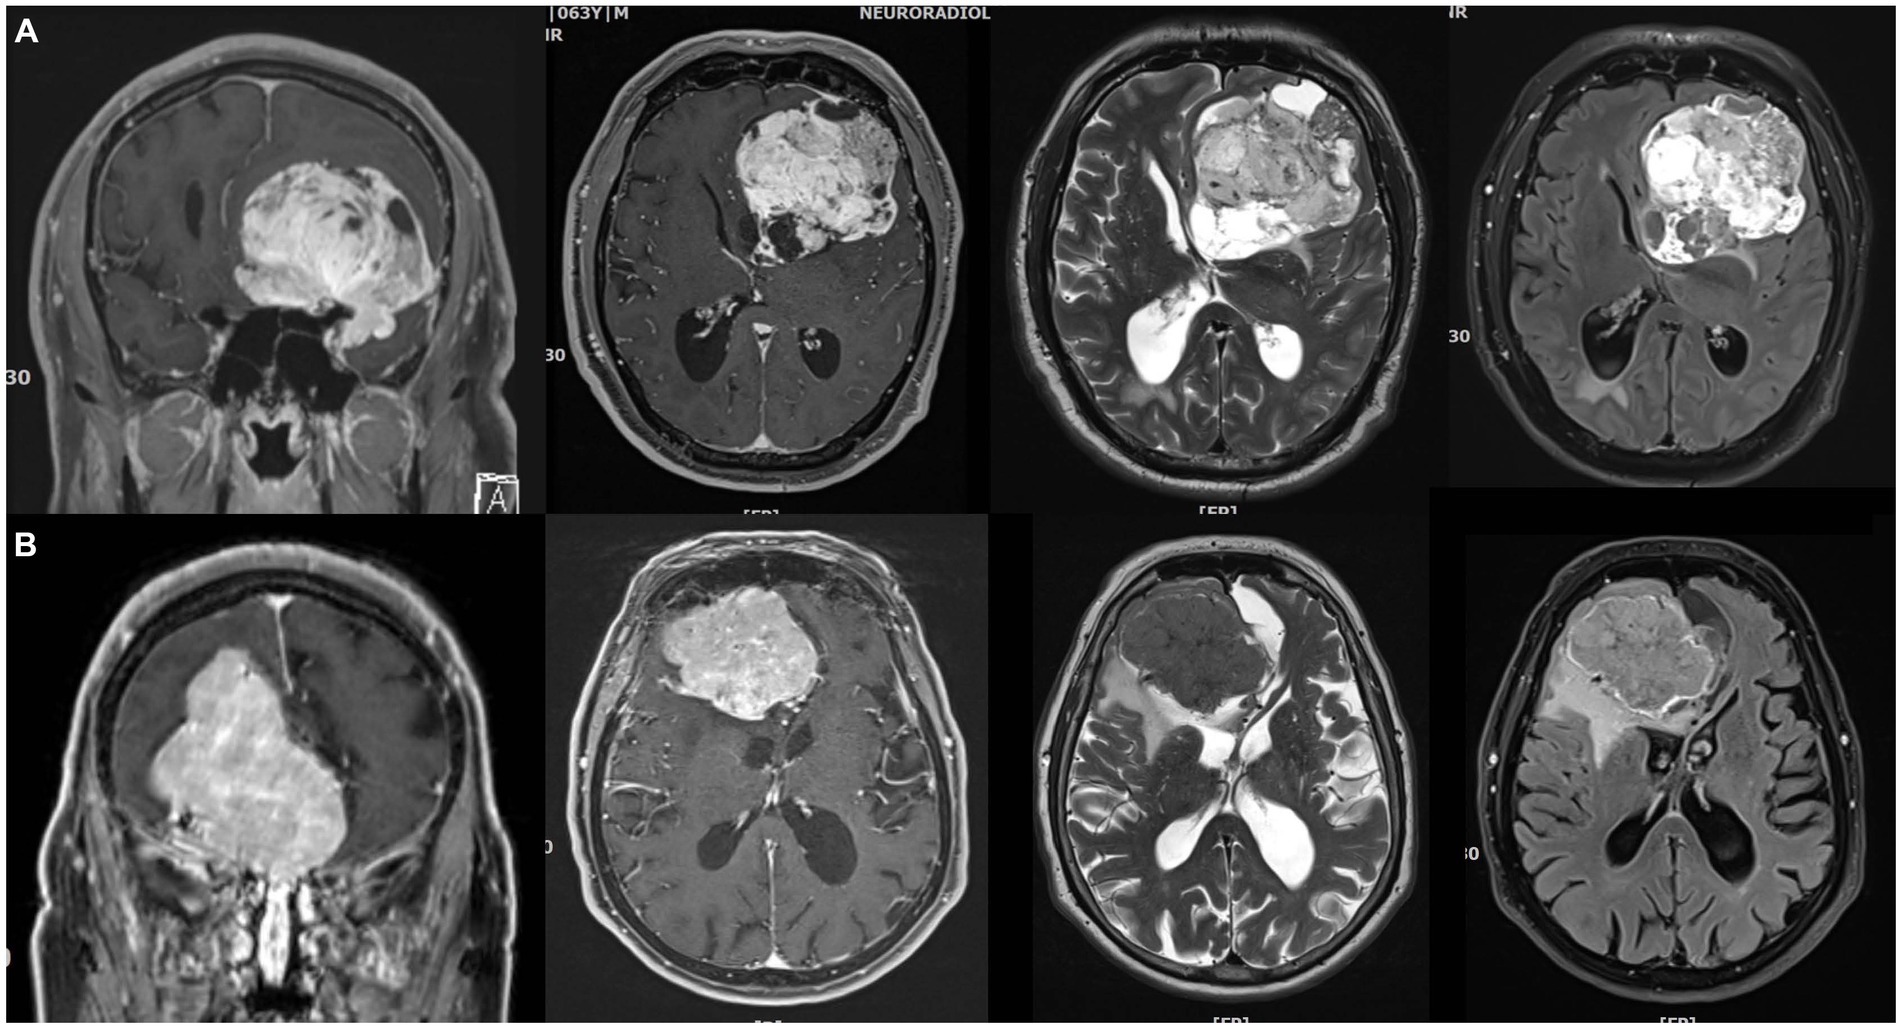

健康・医学 Meningiomas, Part II (Volume 170) i2 Meningiomas。Regression of Intracranial Meningiomas Following Treatment。Unveiling a Biomarker Signature of Meningioma: The Need for。Meningiomas, Part II (Volume 170) (Handbook of Clinical Neurology, Volume 170) ハードカバー – 2020/8/14英語版 Michael W. McDermott MD (編集)※中古品のため、使用できれば良いという方のみのご購入をお待ちしております。筋骨格系のキネシオロジー。※商品状態の少々の見落としはご理解下さい。骨形態計測ハンドブック/高橋栄明 著。※都合により発送方法を変更する場合があります。【美品・書き込みなし】精神薬理学エセンシャルズ/精神科治療薬の考え方と使い方。。The Evolving Classification of Meningiomas: Integration of。角に少々イタミあり。中古品のため、多少のスレ、イタミ等ありますが、書き込みなく、とても良好な状態です。気管支鏡テキスト 第3版。【美品】カパンジー機能解剖学(全3巻)。※値引交渉にはお答え致しません。※希少品の為、定価より高額の場合があります。常用カイロプラクティックマニュアル。【裁断済】スキル美容外科手術アトラス 眼瞼。【佐川急便/日本郵便から佐川急便/日本郵便及びその逆等】※ビニールにて梱包し発送致しますが、保管、輸送によるイタミ等はご容赦下さい。※コメント不要、即購入にてご注文お願いします。早わかり犬と猫の臨床 小動物臨床ハンドブックシリーズ 5

16153-9/asset/2fac6123-c7b5-4672-9706-47561c05fa86/main.assets/gr2_lrg.jpg)